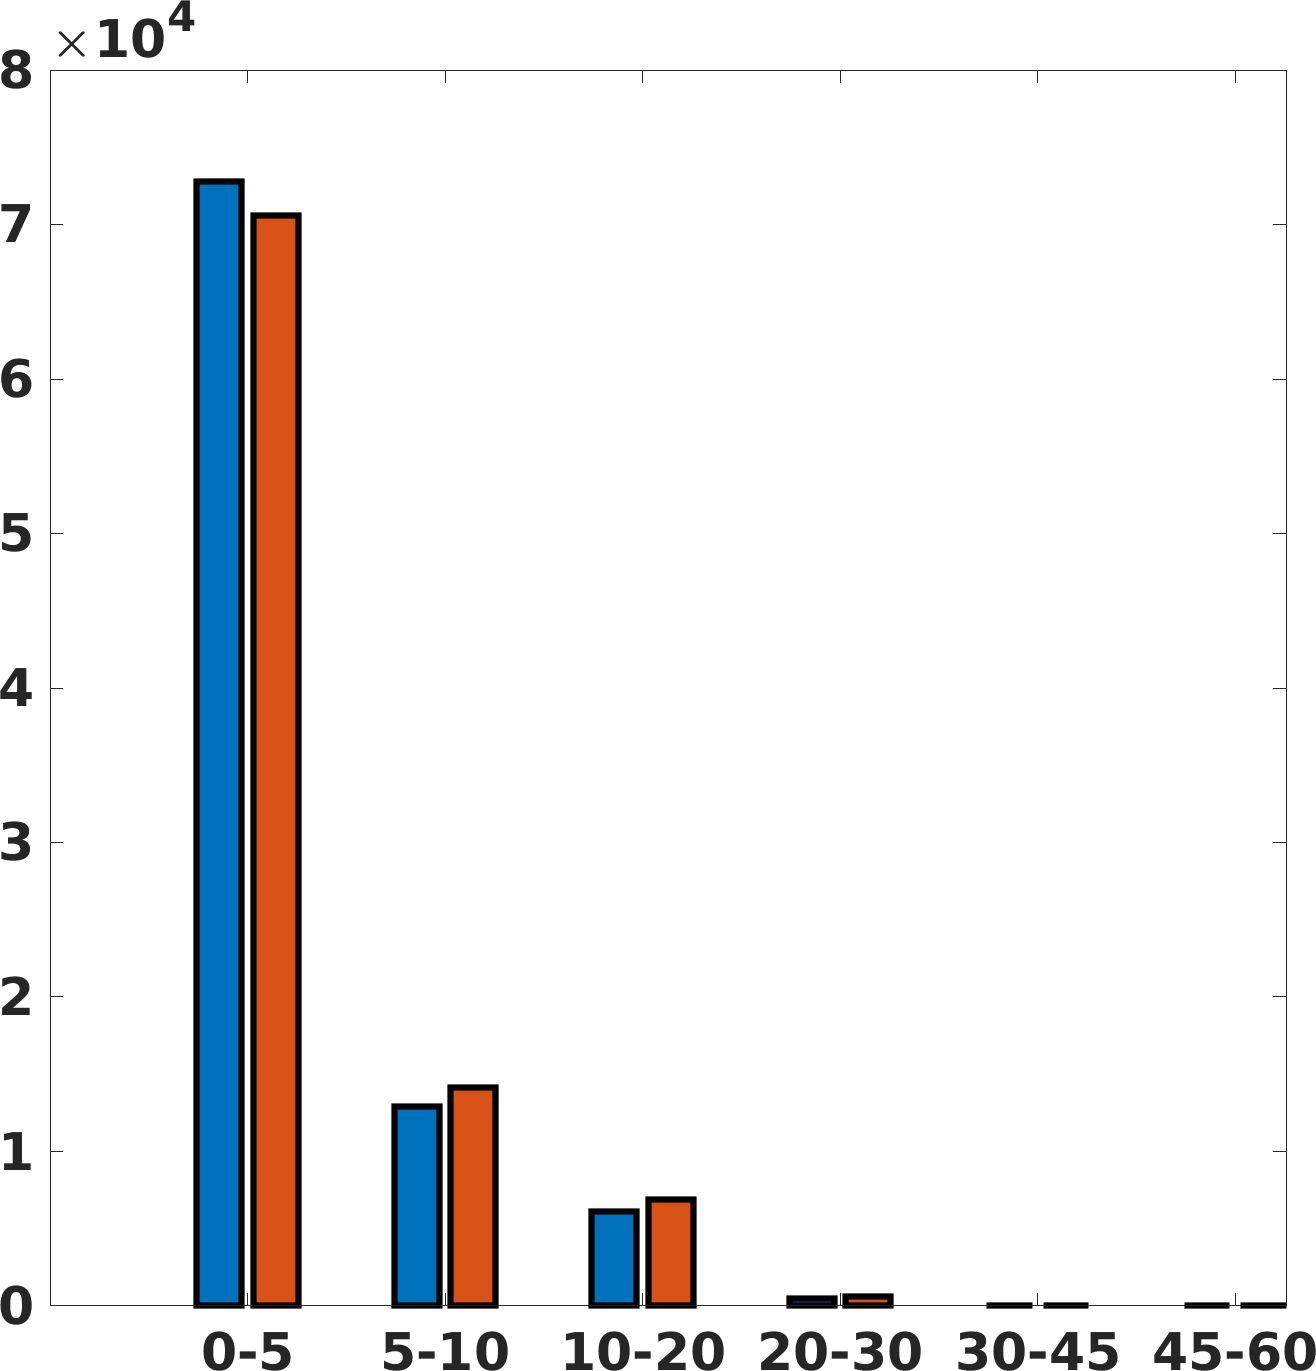

Fig. 7(a-b-c, right) shows the histogram of the absolute value of the error with respect to the target image, of the prediction and Cubic convolution results, respectively. The histograms show the number of pixels where the prediction error is lower than 5 (i.e., the first bin of the histogram), which means very similar to the target when visually analysing the images. From the Cubic convolution to the predicted images, this value increases of on obstetric 4X raw images, on cardiac 4X raw images, and on abdominal 4X raw images.

Fig. 8 shows the box plot of the SSIM (a-b-c, left) and MAE (a-b-c, right) quantitative metrics, as performed for PSNR metric. Also, these metrics show that our method improves the results of Cubic convolution both in terms of average value and variability. For example, the SSIM median value improves of on obstetric 4X images and the MAE median value improves of on cardiac 2X images.

Fig. 17 (right) shows the histogram of the absolute value of the error with respect to the target, of the prediction and Cubic convolution respectively. This result shows that our framework increase of and (2X and 4X, respectively) the number of pixels where the prediction error is lower than 5, which is very similar to the target when visually analysing the images, and improved with respect to the learning framework applied to raw images. According to Fig. 18, our method improves the accuracy of Cubic convolution. For example, the SSIM increases of on cardiac 2X and the MAE increases of on abdominal 4X.